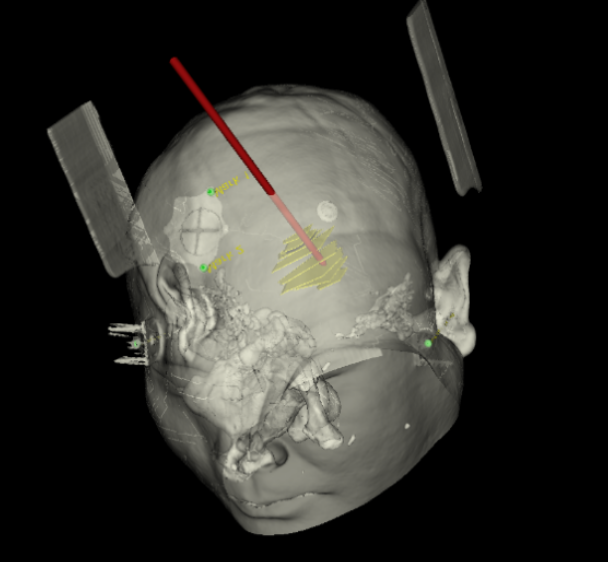

術前韓帥醫生使用“睿米”制定手術規劃

手術規劃在機器人軟件上制定完成